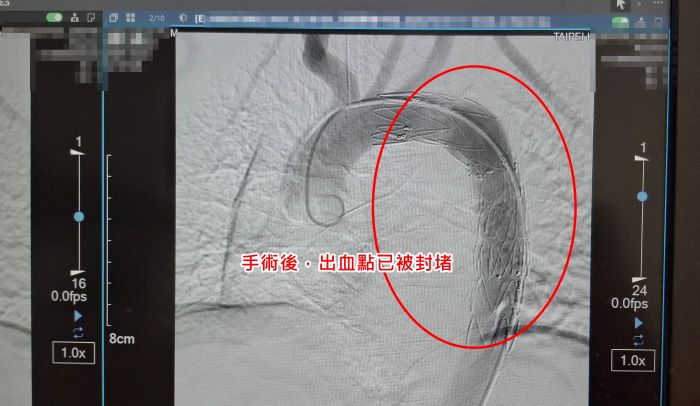

院方緊急會診心臟血管外科醫師孟繁傑,評估後立即施行「胸主動脈腔內血管支架置放手術」,僅在腹股溝處開出不到1公分的小傷口,將支架透過導管送入主動脈破裂處封堵出血點,成功解除致命危機。廖先生術後恢復順利,目前已平安出院。

孟繁傑表示,近年來,主動脈腔內血管支架置放手術逐漸成為主流治療方式。醫師只需從腹股溝股動脈置入導管,將金屬支架精準送到破裂位置撐開血管並封住破口,不僅傷口小、手術時間短,也能降低出血與併發症風險。目前此項治療方式已被美國血管外科學會列為主要治療建議,台灣健保也已納入給付,讓患者能以較低負擔接受先進治療。

孟繁傑說明,過去若破裂點接近分支血管,除了置放主動脈支架外,還可能需要人工血管繞道手術,或進行血管內「煙囪支架」技術,以維持分支血管供血。新型分支支架問世後,可一次完成治療,降低支架內滲漏風險,也避免額外手術傷口,進一步縮短手術時間並減少術後疼痛與併發症。